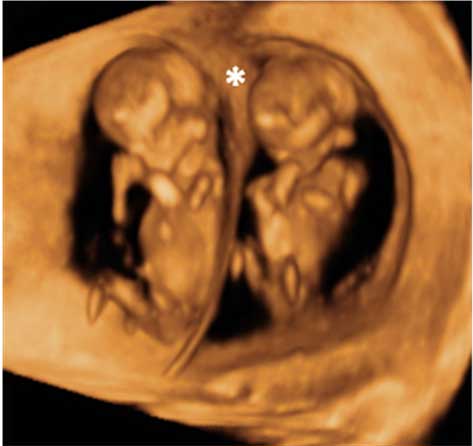

Este bebé, cuya edad gestacional es de sólo 12 semanas, muestra una gran vitalidad de movimientos, a pesar de que el cordón umbilical está peligrosamente situado a la altura del hombro y probablemente alrededor del cuello. El feto parece estar peleándose, como si intentara liberarse de la "atadura" del cordón umbilical.

Ecografía 4D de feto de 12 semanas con cordón umbilical al hombro